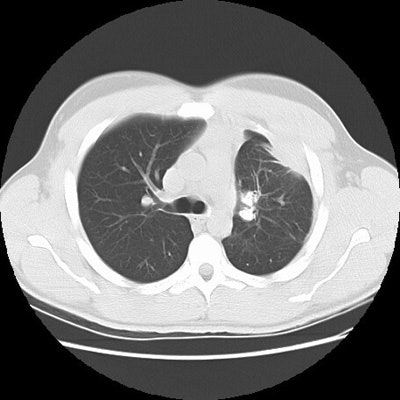

Rounded atelectasis in a patient with prior granulomatous infection

Asbestos related pleural disease is not the only cause of rounded atelectasis. The patient shown in the images below had a prior granulomatous infection with densely calcified left hilar adenopathy. There is extensive plerual thickening seen along the left anterior pleural surface. Rounded consolidated lung can be seen to abut this area of pleural thickening. Lung markings "swirl" into the area of abnormality. There is shift of the mediastinal structures to the left consistent with volume loss.